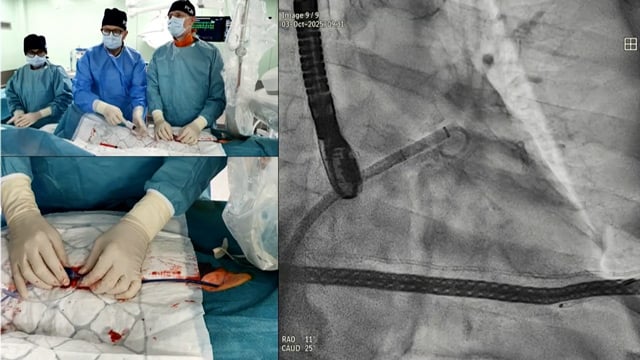

LIVE demonstration from Universitario Clínico San Carlos - Madrid, Spain: TAVI in a patient with high embolic risk

21 May 2019 – From EuroPCR 2019